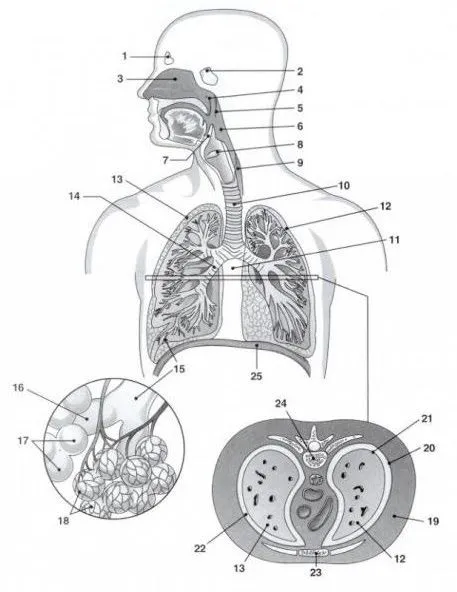

Esquema del aparato respiratorio con nombres

Explora nuestro esquema detallado del aparato respiratorio con nombres, ideal para estudiar y aprender sobre sus partes y funciones.

Esquema del sistema respiratorio con los nombres de sus partes ...

Esquema del aparato respiratorio, Órganos del aparato respiratorio ...

Esquema con nombres del sistema respiratorio - Uma Pergunta

APARATO RESPIRATORIO Y RESPIRACIÓN | Bioroca